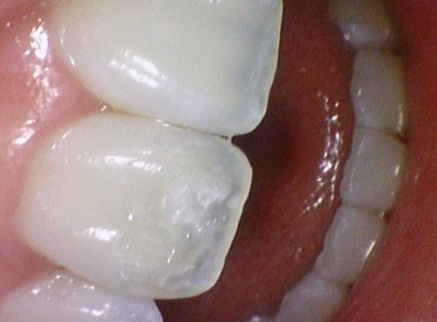

화이트스팟

치아 표면에 불투명하게 보이는 흰색 반점. 바로 화이트스팟 White Spot, White stain입니다.

교정장치 제거 후 하얗게 얼룩처럼 보이는 경우도 있고

원래 그 치아가 날때부터 화이트스팟이 있는 경우도 있고

초기 충치로 아직 구멍은 없지만 미네랄이 빠져나간 상태 등등

원인은 다양합니다.